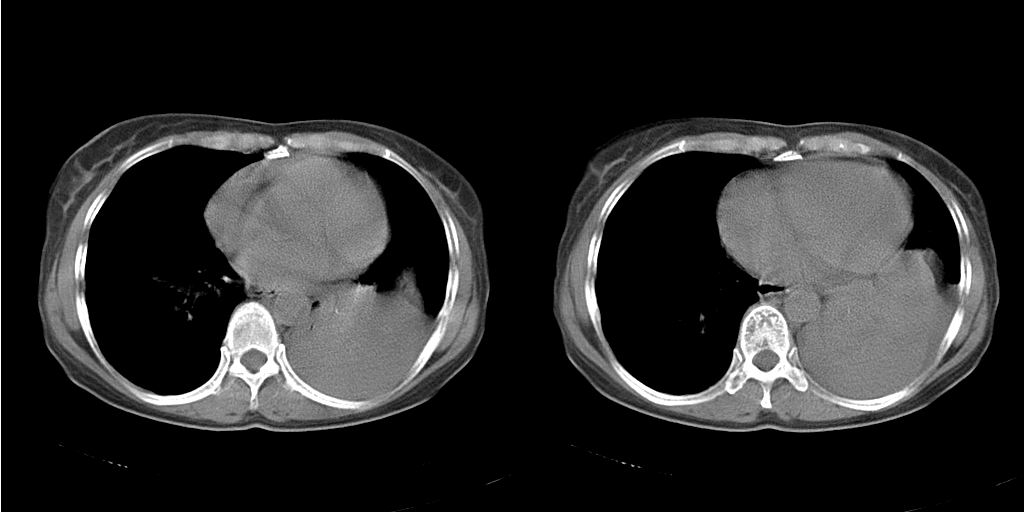

以下是引用dyqct在2007-1-23 15:01:00的发言:[br]左肺下叶实变、略萎陷,近肺门下部密度不均。上腔静脉后及隆突前见肿大淋巴结。余未见异常。[br]考虑:1、左肺下叶中心型肺癌伴肺不张、纵隔淋巴结转移;[br] 2、建议增强扫描并做任意平面重建确定肿块范围及支气管受累情况。

以下是引用同在2007-1-23 19:59:00的发言:[br]左肺下叶中央型肺癌伴肺不张及纵隔淋巴结转移.